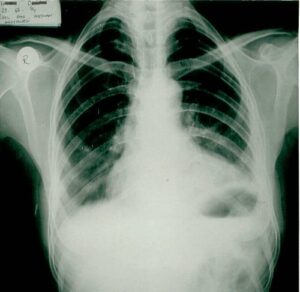

Solid Tumor Research

Innovative approaches in lung, breast, colorectal, and other solid tumors. Combinations of targeted therapy and immunotherapy.